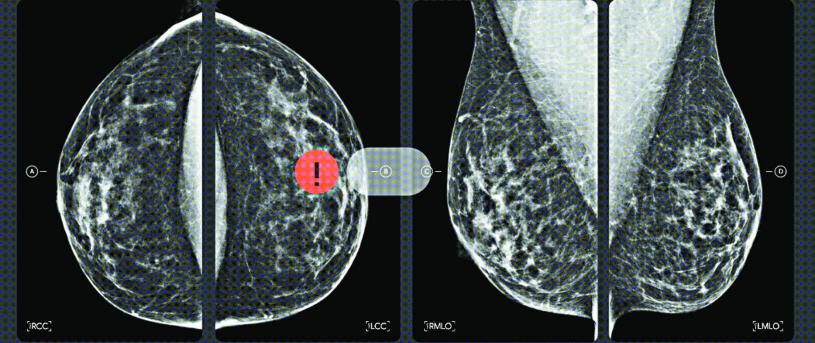

谷歌宣佈授權醫學技術公司iCAD使用它的人工智能(AI)模型進行乳癌篩查。這是谷歌首次就這種技術提供授權,希望最終可帶來更準確的乳癌檢測和風險評估。

iCAD打算將谷歌乳房X光檢查AI研究模型納入它現有工具之中。首款工具是iCAD的ProFound AI,對「數位化三維多切面斷層乳房攝影」(DBT)的圖像進行分析,掃描DBT圖像尋找惡化軟組織密度和鈣化。iCAD亦計劃利用谷歌的模型配合它的風險評估工具使用。該公司表示,此舉將提供適合每人的個性化乳癌風險評估。